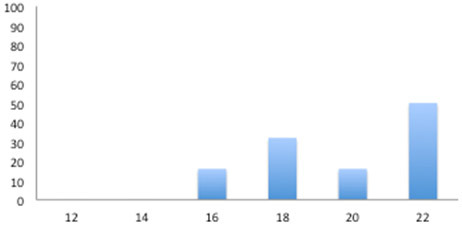

Si è deciso comunque di realizzare un profilo sierologico trasversale per determinare la dinamica dell'infezione da Lawsonia intracellularis in questa piramide di produzione.

Si raccolsero 6 sieri ad intervalli di 2 settimane dalla settimana 12 alla 22.

Ovvero, su 36 sieri si realizzò il test ELISA nei quali 7 risultarono positivi, tutti successivi alla settimana 16.

Sieroprevalenza

Vale a dire che il momento dell'infezione si potrebbe situare verso la 14° settimana, coincidendo con il caso sopra descritto.